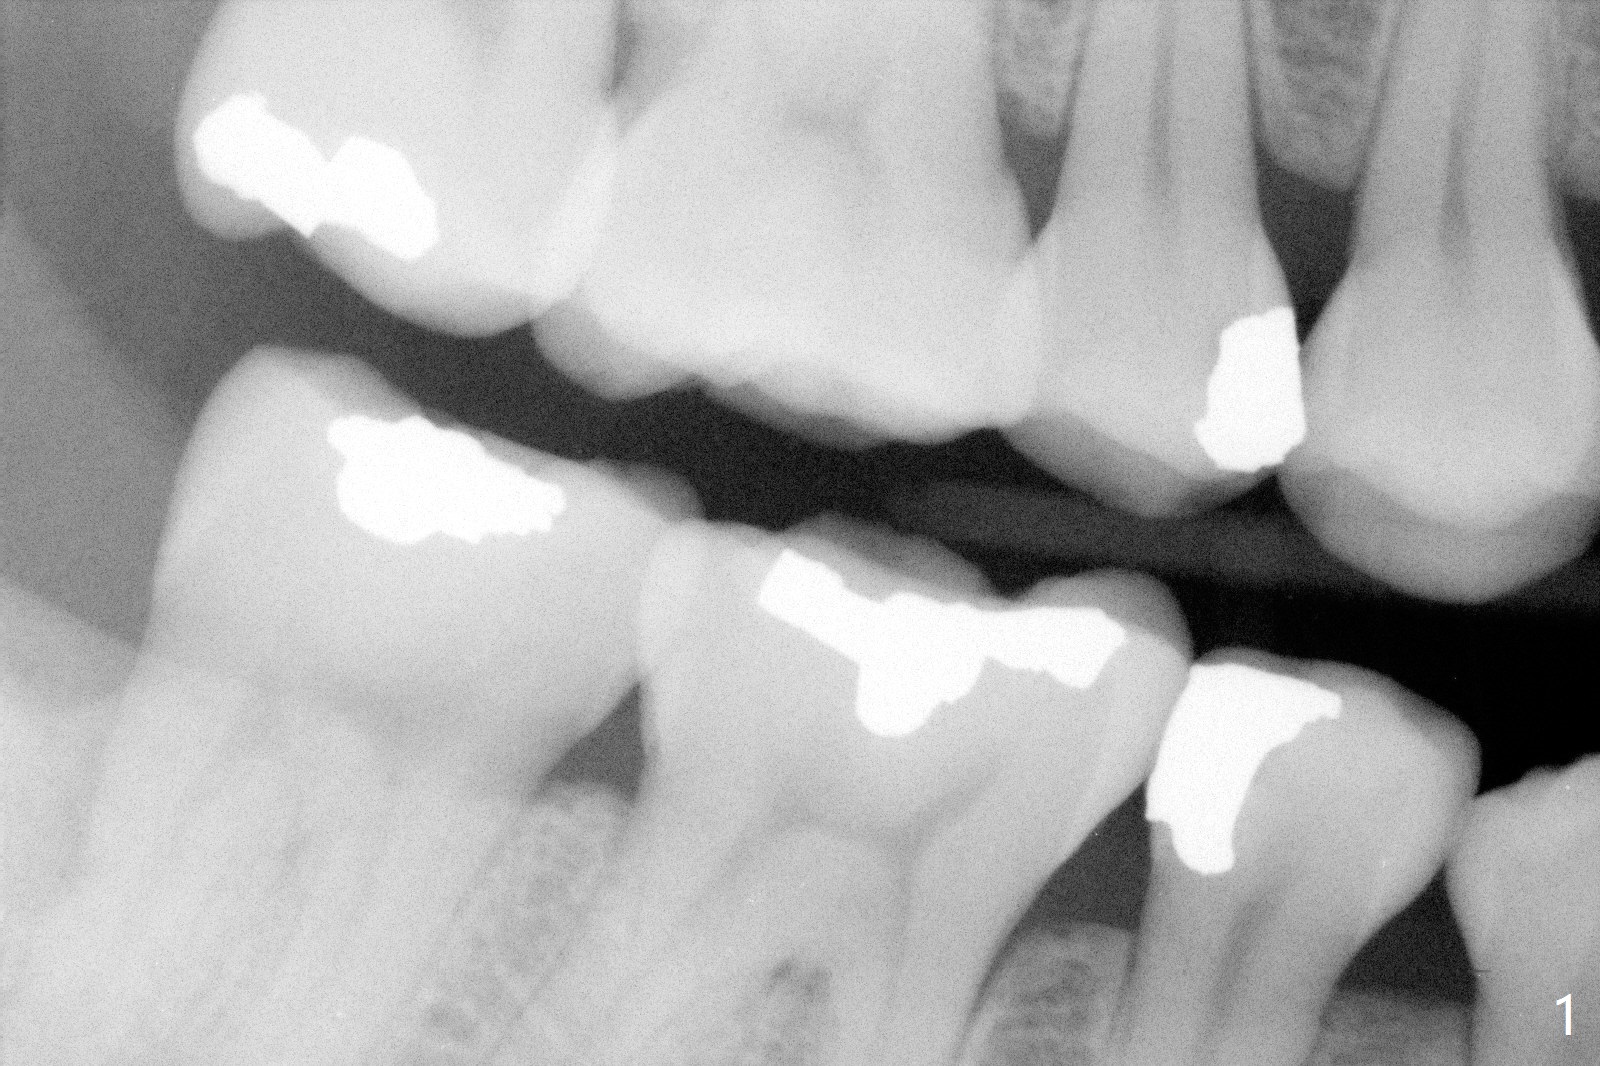

A 29-year-old woman presented to office with multiple amalgam restoration 7 years ago. The tooth #4 developed acute pulpitis 7 months later (Fig.2). The tooth has 2 fused canals; after RCT, composite was placed; after discussion, the patient chose no crown (Fig.3). There is no recurrent periapical radiolucency or tooth fracture 2.5 (Fig.4) or 6.5 (Fig.5,6) years postop.